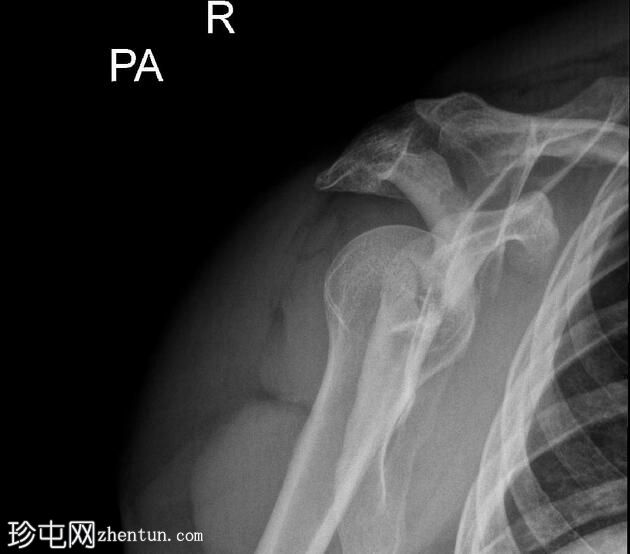

3.jpeg

斜位

右侧肩胛骨骨折,累及肩胛盂、肩胛颈和肩胛体。肱骨头与肩胛窝对位良好,提示无肩关节脱位。

肩部和肩胛骨周围有弥漫性软组织肿胀。

本例X光片显示骨折累及肩胛盂、肩胛颈和肩胛体,提示力量显著通过肩胛带传递。肩胛盂受累尤为重要,因为它可能损害盂肱关节的稳定性和关节的一致性。

肩关节无脱位且肱骨头排列完整是有利的发现。然而,由于解剖结构复杂且可能在关节内延伸,建议进行CT扫描以更好地明确骨折形态并指导手术计划。